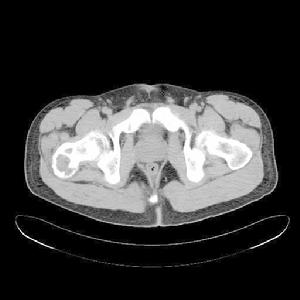

2、CT:

動脈瘤樣骨囊腫1.為囊狀膨脹性骨破壞,其內充滿液體密度,均質,無鈣化,可見骨性間隔。

2.局部骨皮質變薄,骨骼膨大。 3.增強掃描可見有粗大的供血血管,病灶可見斑片狀明顯強化。

4.囊內若顯示有液-氣液平面,上為水樣低密度,下為略高密度,則為典型表現。

CT能顯示整個椎體ABC的全貌和其內的細微結構,其良好的密度解析度對顯示病灶骨梁狀分隔或骨嵴非常敏感,另外也可檢測病灶內液—液面(FFL)的存在,為病灶的定位定性有很大的幫助。Davies研究表明,使用較窄的窗寬(<100Hu)比較容易對液面進行觀察,病灶內部其上方為水樣低密度,下方為未凝固的血液高密度,讓患者靜止1分鐘後再掃描可以更好顯示液平面。